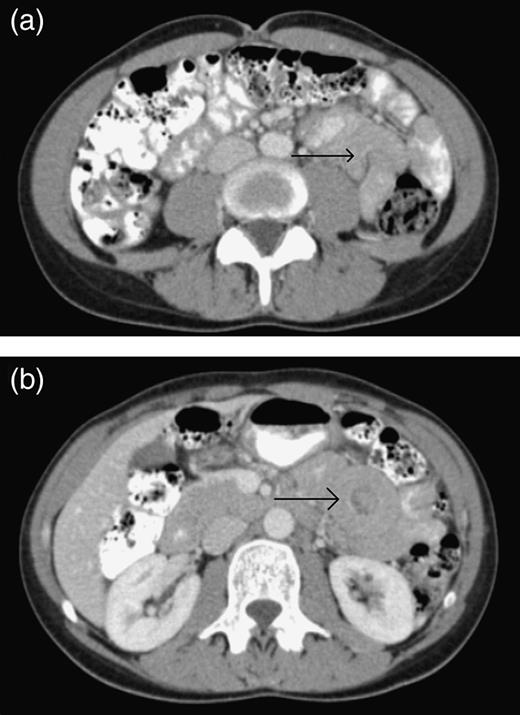

A 41-year-old female presented with 3 weeks of intermittent crampy epigastric abdominal pain, nausea and diarrhea. She was able to tolerate a liquid diet but not solids. She had one episode of vomiting and lost 6 lbs over the course of 3 weeks. Her vital signs, physical examination and laboratory studies were unremarkable. She did not have a history of prior abdominal surgery or malignancy. A CT scan demonstrated two areas of small bowel intussusception (Fig. 1A and B), without evidence of bowel obstruction or mass. The patient underwent exploratory laparoscopy using a 5 mm 30° camera and two 5 mm working ports. Six separate regions of intussusception within the small bowel were discovered between 55 and 130 cm from the ligament of Treitz. All areas of intussusception were short and witnessed to undergo spontaneously reduction (Fig. 2A and B), except for one (Fig. 3), which was resected through a mini-laparotomy. There was no obvious evidence of masses, adhesions or serosal abnormalities along the small bowel. There were prominent lymph nodes noted in the small bowel mesentery (Fig. 4). The postoperative course was uneventful and she was discharged 4 days after her operation. She had resolution of symptoms and had no recurrence after 3 years of follow-up. Pathologic examination of the small bowel demonstrated no evidence of malignancy, lead point, pathologic changes or sprue. Likewise, there was no evidence of acid-fast organisms, fungal or helminth parts identified. The enlarged mesenteric lymph nodes demonstrated reactive follicular hyperplasia and multifocal non-necrotizing lipogranulomas.

(a) The CT scan of the abdomen demonstrating an area of small bowel intussusception (arrow) resulting in a mushroom sign. (b) The CT scan of the abdomen demonstrating an area of small bowel intussusception (arrow) resulting in a target sign.